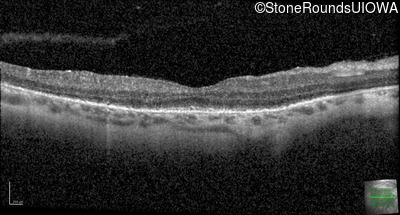

Optical Coherence Tomography - Left - 20/50 +1

Exemplar / OCT Stack